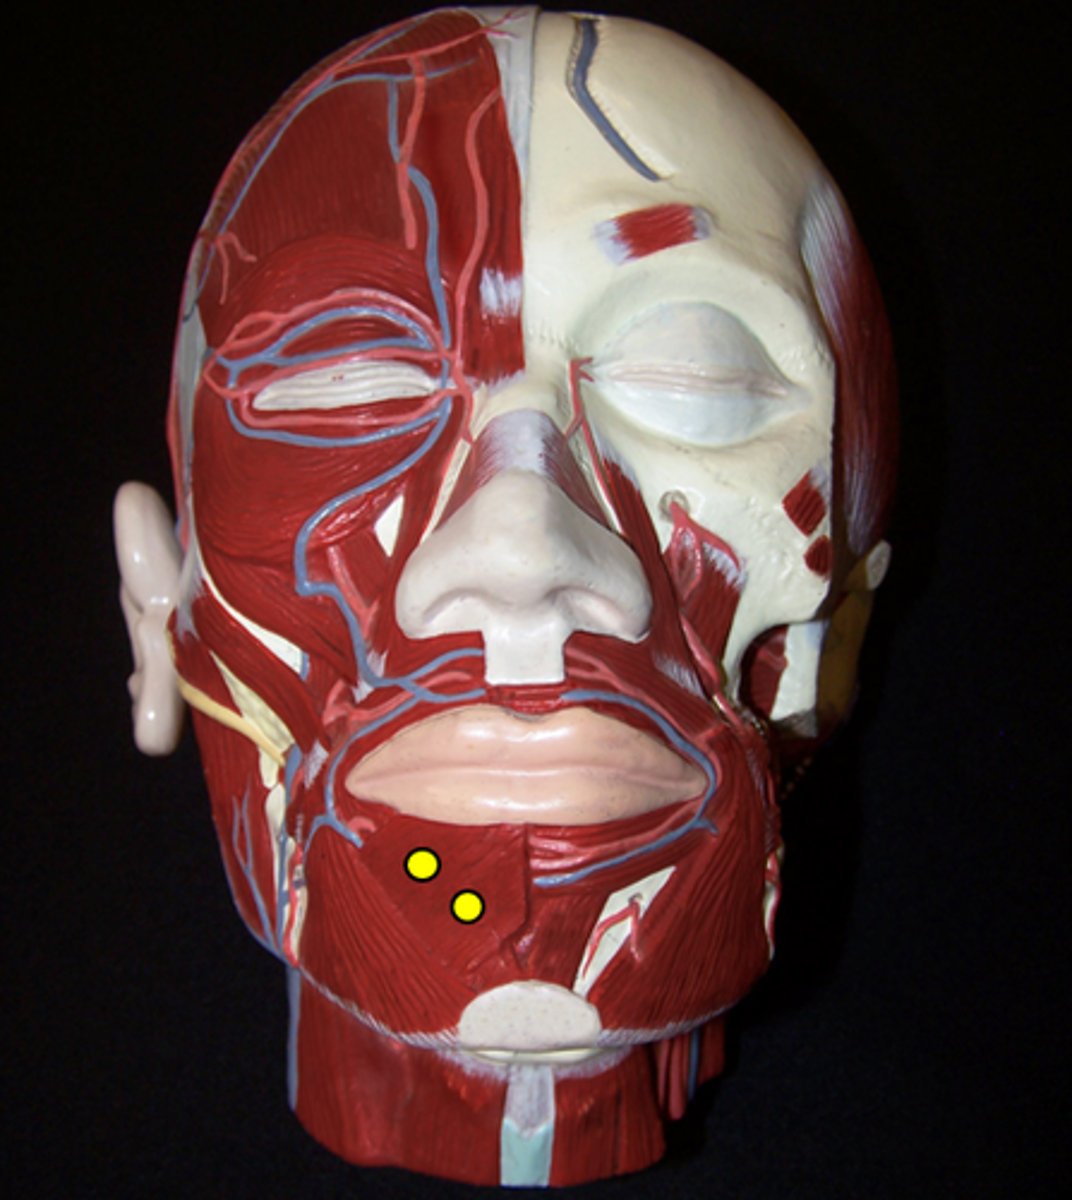

Depressor Labii Inferioris

Mentalis